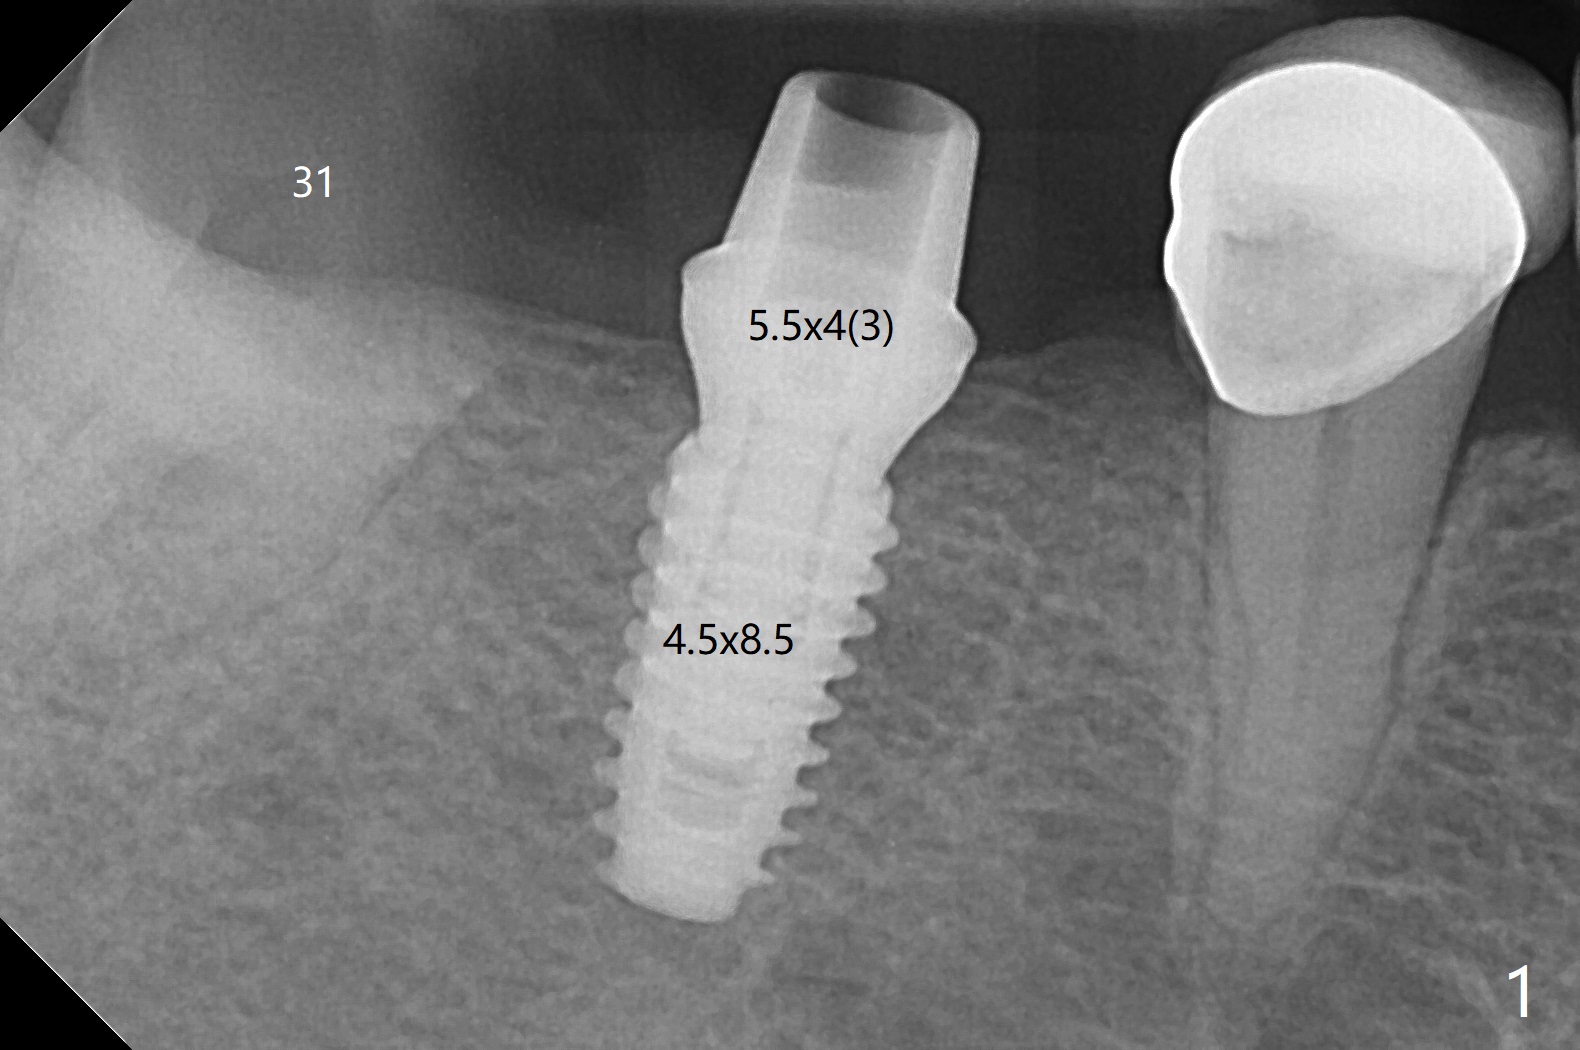

When the guide is seated for #30 implant, it appears that the tissue punch may remove all of the buccal keratinized gingiva. Therefore incision is made with flap reflection. The bigger advantage of flap surgery is that as the implant is placed, the lingual crest is found to be the lowest (which is the most likely to be neglected with flapless approach) so that bone graft can be easily placed. In contrast the mesial crest is the highest. For seating of a cemented abutment (Fig.1) and a healing abutment (Fig.2), profile drills (5.5 and 6.0 mm) have to be used, respectively. Following #31 extraction, Vanilla graft (minor portion) and Osteogen Plug (major portion, most likely no implant in the future) are placed, followed by GEM Cap and 4-0 Chromic Gut suture. After removing the healing abutment 4.5 months postop, a 5.5x4(3) mm cemented abutment is seated completely; it appears that the distal crest resorbs substantially (Fig.3 *). The access hole is distal as related to distal end guide (in fact #31 was used as distal stop before extraction) and radiation interference from #29 crown (Fig.4). The uneven mesial and distal crest may be the main reason for the deviation.